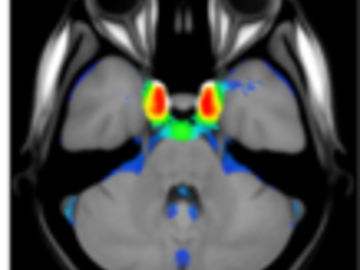

A statistical atlas of cerebral arteries

Magnetic resonance angiography (MRA) can capture the variation of cerebral arteries with high spatial resolution. These measurements include valuable information about the morphology, geometry, and density of brain arteries, which may be useful to identify risk factors for cerebrovascular and neurological diseases at an early time point. However, this requires knowledge about the distribution and morphology of vessels in healthy subjects. the statistical arterial brain atlas described in this work is a free and public neuroimaging resource that can be used to identify vascular morphological changes. The atlas was generated based on 544 freely available multi-center MRA and T1-weighted MRI datasets. the arteries were automatically segmented in each MRA dataset and used for vessel radius quantification. The binary segmentation and vessel size information were non-linearly registered to the MNI brain atlas using the T1-weighted MRI datasets to construct atlases of artery occurrence probability, mean artery radius, and artery radius standard deviation. This public neuroimaging resource improves the understanding of the distribution and size of arteries in the healthy human brain.

The statistical atlas consists of four image files in the niftii format and in MNI reference space (0.5 mm^3). These files include the TOF MRA average atlas (tofAverage.nii.gz), the vessel probability atlas (vesselProbabilities.nii.gz [in %]), the mean artery radius atlas (vesselRadius.nii.gz [in mm]), and the standard deviation of the artery radius atlas (vesselRadiusStd.nii.gz [in mm]). All images are saved using float values. The TOF MRA and T1-weighted datasets used for atlas generation can be downloaded from the original sources.